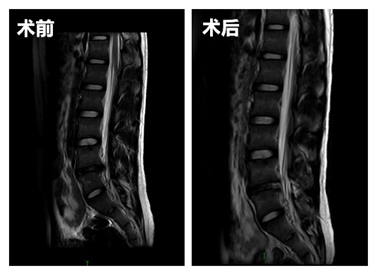

患者小翟是个20岁的年轻小伙子,来我院就诊时,左下肢疼痛难忍活动受限,一直卧床休息,严重影响了生活质量,主诊医师陈海龙团队接诊后,为小翟完善相关检查,诊断为L4/L5椎间盘突出,又经过详细的术前评估,最后决定利用UBE技术为患者减轻痛苦。术后患者疼痛症状消失,第二天便可以下床活动。

UBE技术即单侧双通道内镜技术(unilateral biportal endoscopic technique),适用于颈椎、胸椎、腰椎的退行性变,是一种新兴的脊柱微创手术技术。与椎间孔镜的单通道不同,该技术通常建立两通道,一个为观察通道,一个器械操作通道。观察通道一般用0度或30度关节镜,操作通道可以应用常规的脊柱外科及运动医学的器械如刮匙、磨钻(关节镜磨头)、关节镜刨刀、关节镜射频刀头、椎板咬骨钳、髓核钳、神经拉钩等,两个通道的操作互不干扰,使脊柱微创手术的操作更加便捷灵活。

此外,相对于传统的切口手术,UBE技术手术时仅有两个长约1cm的小切口,创伤明显减少,术中出血少,背部肌群损伤小,术后效果立竿见影,减少了并发症的发生,缩短了患者的住院时间,很大程度上帮助了患者早日回归正常生活。